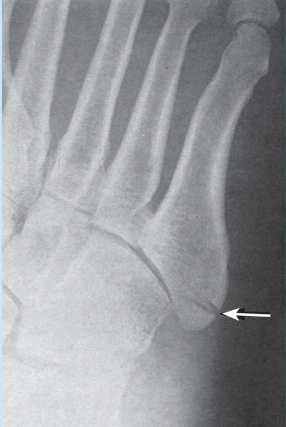

9

Q

Which bone is fractured? -potential situation in which fracture could occur

A

-Lateral aspect of 5th metatarsal -Dancer fracture